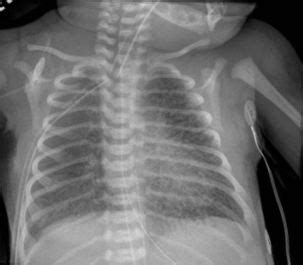

Spotting Pulmonary Interstitial Emphysema (PIE) isn’t always straightforward, as the symptoms can mimic other respiratory issues, especially in infants. However, doctors are trained to look for specific clues. In newborns , persistent respiratory distress that doesn’t improve with standard treatments is a major red flag. This can manifest as rapid breathing (tachypnea), grunting sounds with each breath, nasal flaring, and a bluish tint to the skin (cyanosis) due to low oxygen levels. You might also notice that the baby’s chest seems unusually distended or